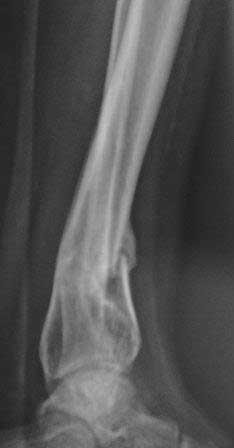

[Ortho] Вялоконсолидирующаяся перелом дистального метадиафиза костей левой голени

Пациентка 32 года, травму получила в результате ДТП, лечилась в гор.б-це №? Москвы с 19.07.по04.08.11г скелетным вытяжением, после наложена гипсовая повязка,(р-снимок 1,2.) после спадения отека гипс переведена в циркулярную, (видимо на другой вид лечения не хватило средств), гипс снят 19.11.11г(снимок-3)

.Жалобы на боли при ходьбе через несколько шагов, увеличение отека в голени и г/стопном суставе, боли ноющего и неприятного характера, хромота, при осмотре отечность голени в с-н/з и г/с суставе, при пальпации умеренная болезненность в н/з голени, подошвенное сгибание в г/с суставе ограничена и болезненна. Работа связана с ходьбой, просить помочь чтобы не потерять работу. Пока в голове только КДО аппаратом Илизарова, уважаемые коллеги  помогите советом! Доступно БИОС, пластины DCP. и прилагается последние р-снимки.